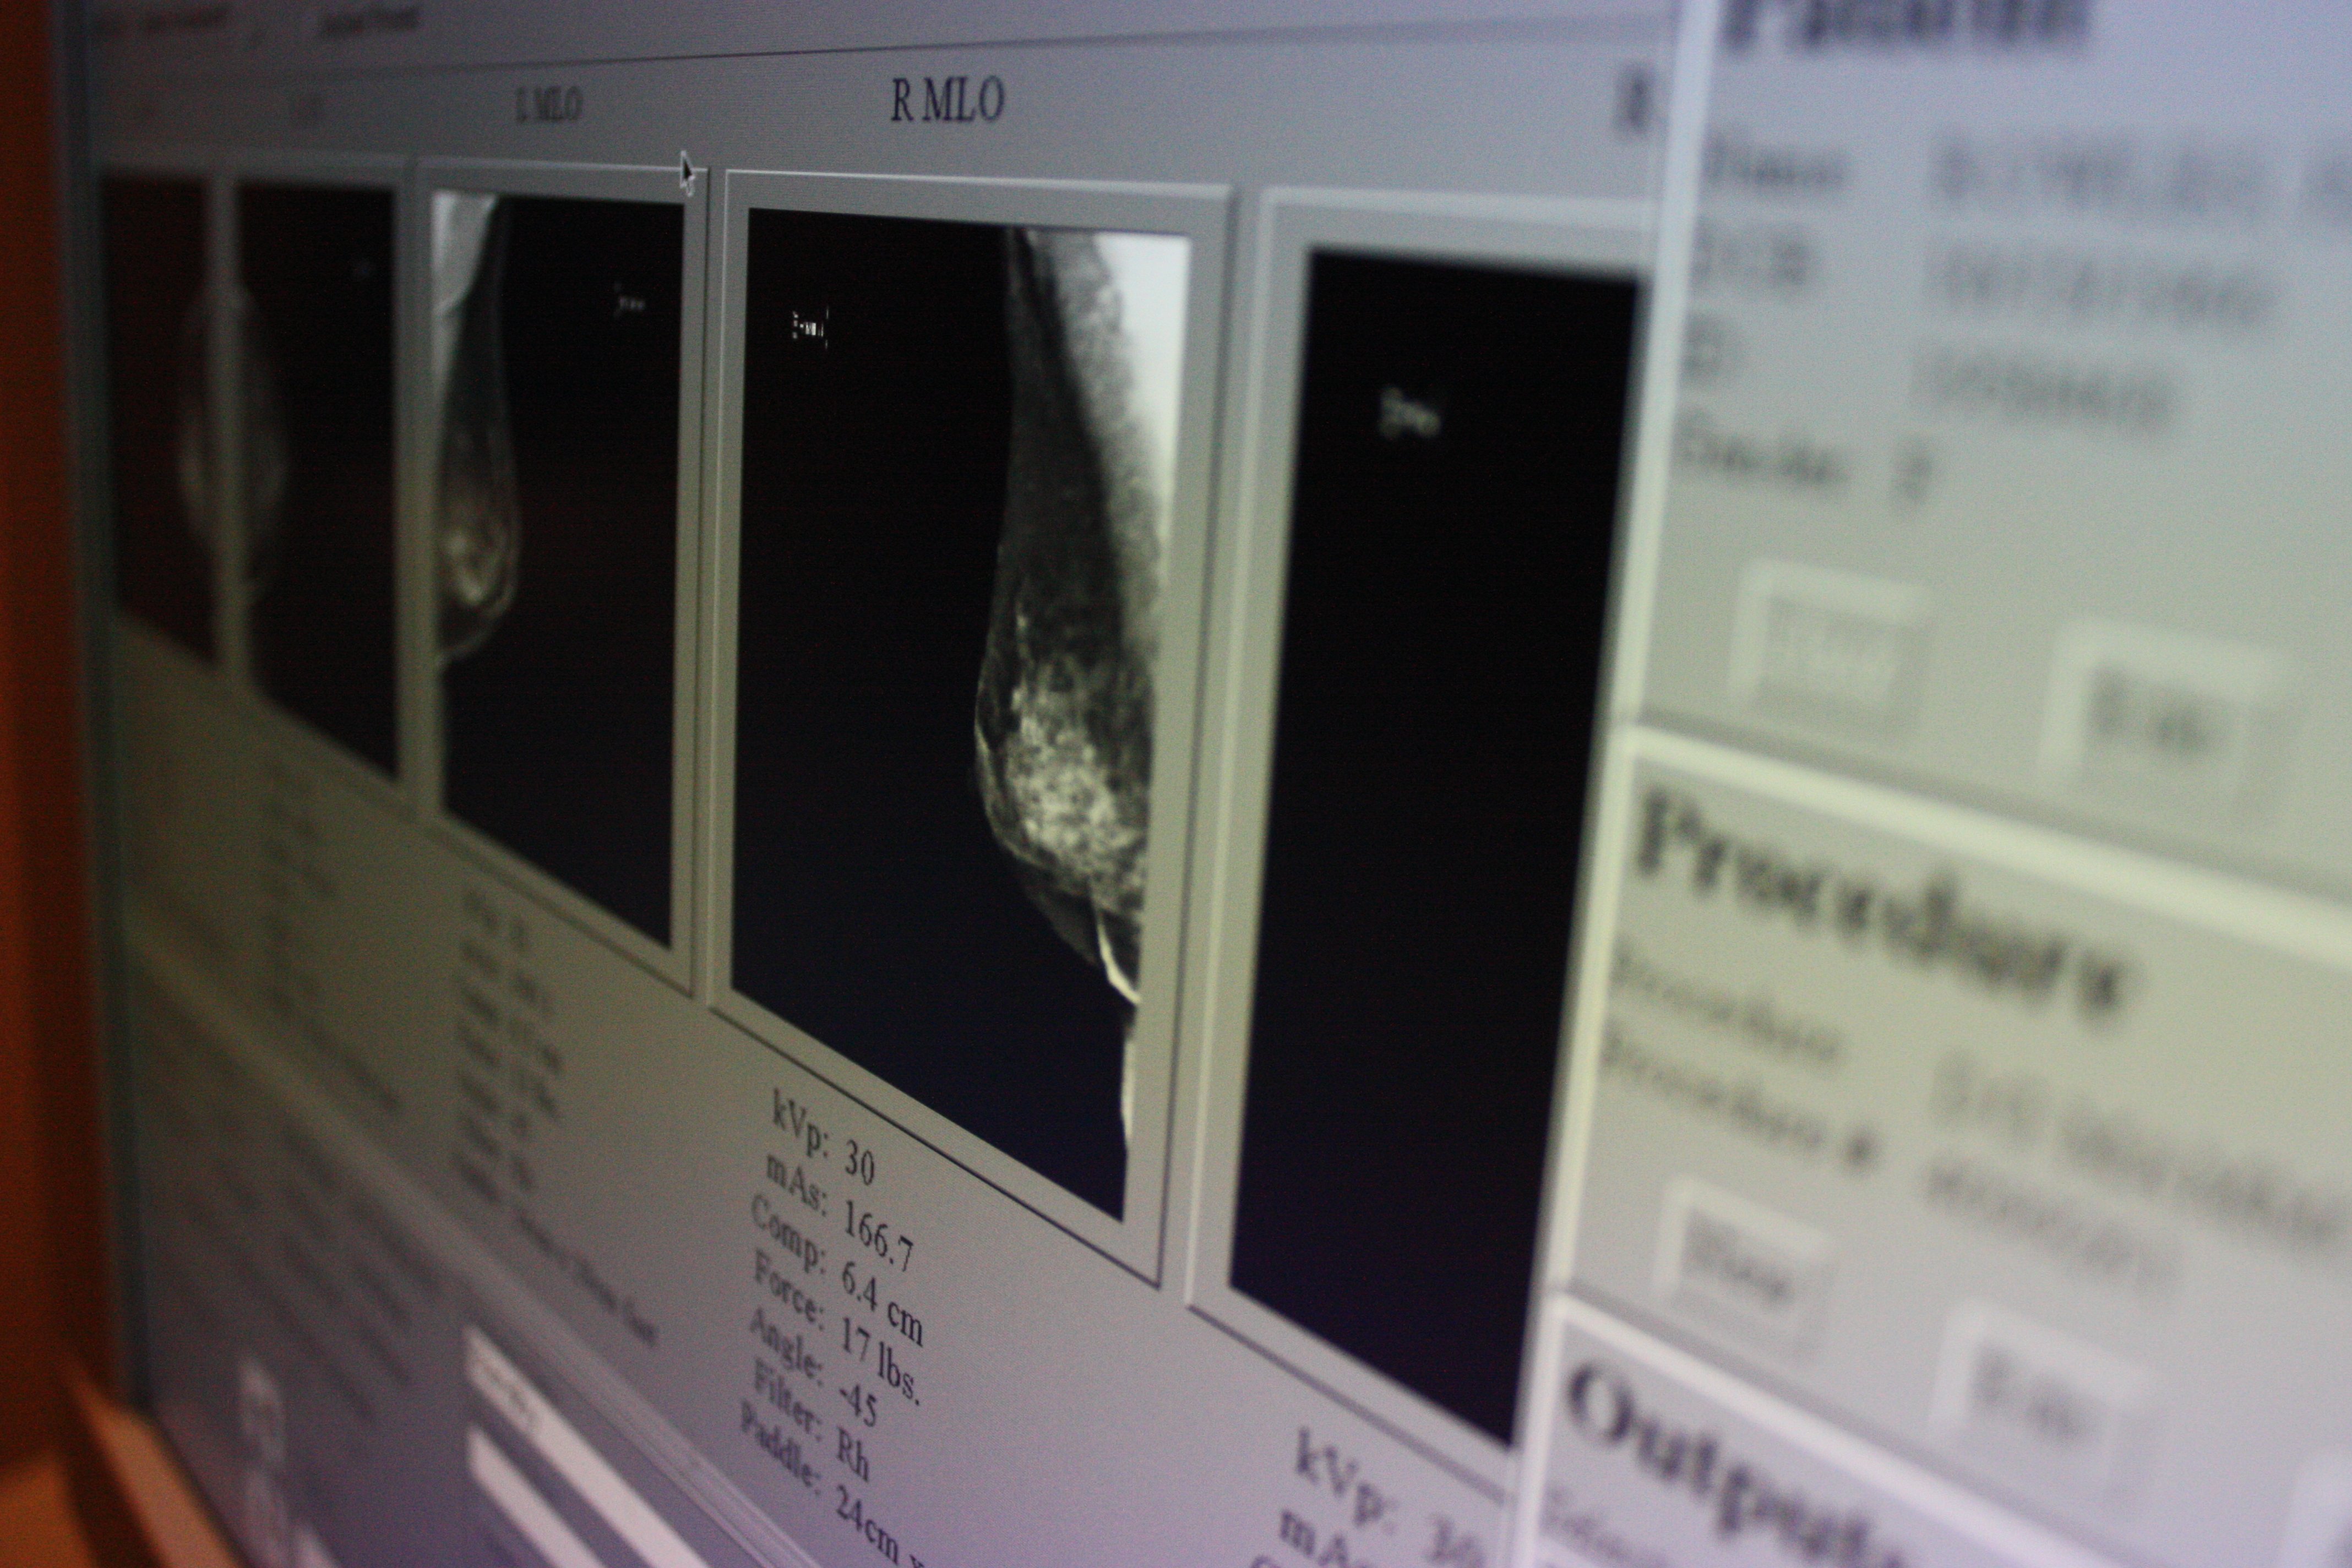

ATLANTA (CNN) — Women who have a false positive result on their mammogram may actually be at slightly higher risk of developing breast cancer over the following decade, according to a new study.

Researchers looked at more than 2 million mammograms that had been performed on women ages 40 to 74 at health clinics across the United States between 1994 and 2009.

About 180,000 of the mammograms were false positives, meaning that the test detected a tissue abnormality but an additional imaging or biopsy test did not support a cancer diagnosis and the women did not develop breast cancer in the year after the mammogram. The remaining tests were true negatives because they did not detect an abnormality and were not associated with the development of breast cancer in the following year.

The researchers found that an additional one woman out of 100 who had a false positive mammogram and followed it up with another imaging test went on to develop breast cancer in the next decade, as compared with women who did not have a false positive result. Among women who had a false positive followed by a biopsy, an additional two out of 100 developed breast cancer. The larger increase in risk in the biopsy group was presumably because these women had tissue that was more abnormal and thus concerning enough for the radiologist to order the more invasive follow-up test.